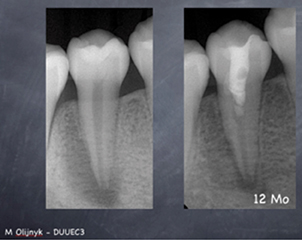

Viendra ensuite le tour de Stéphane Simon qui exposera trois nouveaux concepts dans le domaine de l’endodontie.

Il débutera sa conférence par une présentation en avant-première d’un nouveau système d’irrigation en continu avec une activation en un seul temps. Si jusqu’alors les praticiens procédaient de façon « artisanale », ce nouvel appareil, conceptualisé par Stéphane Simon lui-même, permet d’irriguer tout au long de la préparation du canal de la racine. Deuxième nouveauté en endodontie : l’obturation du système canalaire recourant au concept de monocône. Stéphane Simon présentera les nouveaux matériaux biocéramiques qui permettent de mettre en application ce concept. Il expliquera comment un seul matériau peut remplir et rendre hermétique le canal. Le troisième concept sera basé sur l’ingénierie tissulaire en endodontie régénérative.

- Innovation matérielle et conceptuelle en endodontie

par Stéphane Simon

La plus-value tient en deux mots : nouveautés et révolutions. Les concepts, présentés par trois grands noms de la profession, sont révolutionnaires voire avant-gardistes dans le mode de la dentisterie. Pour ne donner qu’un exemple, l’intervention de David Nisand va à l’encontre des idées reçues en implantologie. Quant à Stéphane Simon et Gil Tirlet, ils repensent les techniques actuelles.

Ils expliqueront comment conserver la pulpe voire la façon dont le praticien peut la régénérer au lieu de la remplacer. Les techniques adhésives qui dépassent largement ce que nous avons vu jusqu’à maintenant, permettent la restauration de délabrements partiels, mais aussi de grands délabrements sur des dents dépulpées ou non, mais avec des pertes de substances importantes.

Le praticien ressortira-t-il de la conférence avec des réponses concrètes et applicatives ?

Oui, bien sûr, car même si certains concepts sont encore très peu pratiqués, la présentation des nouveaux matériaux et machines permettront aux praticiens de s’en servir dès le lendemain matin au cabinet dentaire.